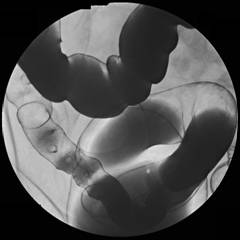

一、什麼是大腸鋇劑檢查(Barium enema)?

大腸鋇劑檢查又稱為下消化道攝影(LGI)。這是針對大腸的特殊X光檢查,包括了直腸、乙狀結腸、下結腸、橫結腸、上結腸、盲腸及闌尾。為使得這些構造能表現在X光片上,將一定量的鋇劑由肛管灌入,然後必須灌入一些空氣進入腸道使其膨脹。

四、檢查方式:

1.檢查時首先請您俯臥在檢查台上,由醫師將肛管插入肛門,醫師灌入適量之顯影劑(鋇劑),並視需要打入適量空氣均勻混合,並依醫師指示於檢查台上做不同姿勢之旋轉。年紀大或行動不便者,最好有家屬陪伴前來或協助攝影‧整個檢查通常需要20~30分鐘。